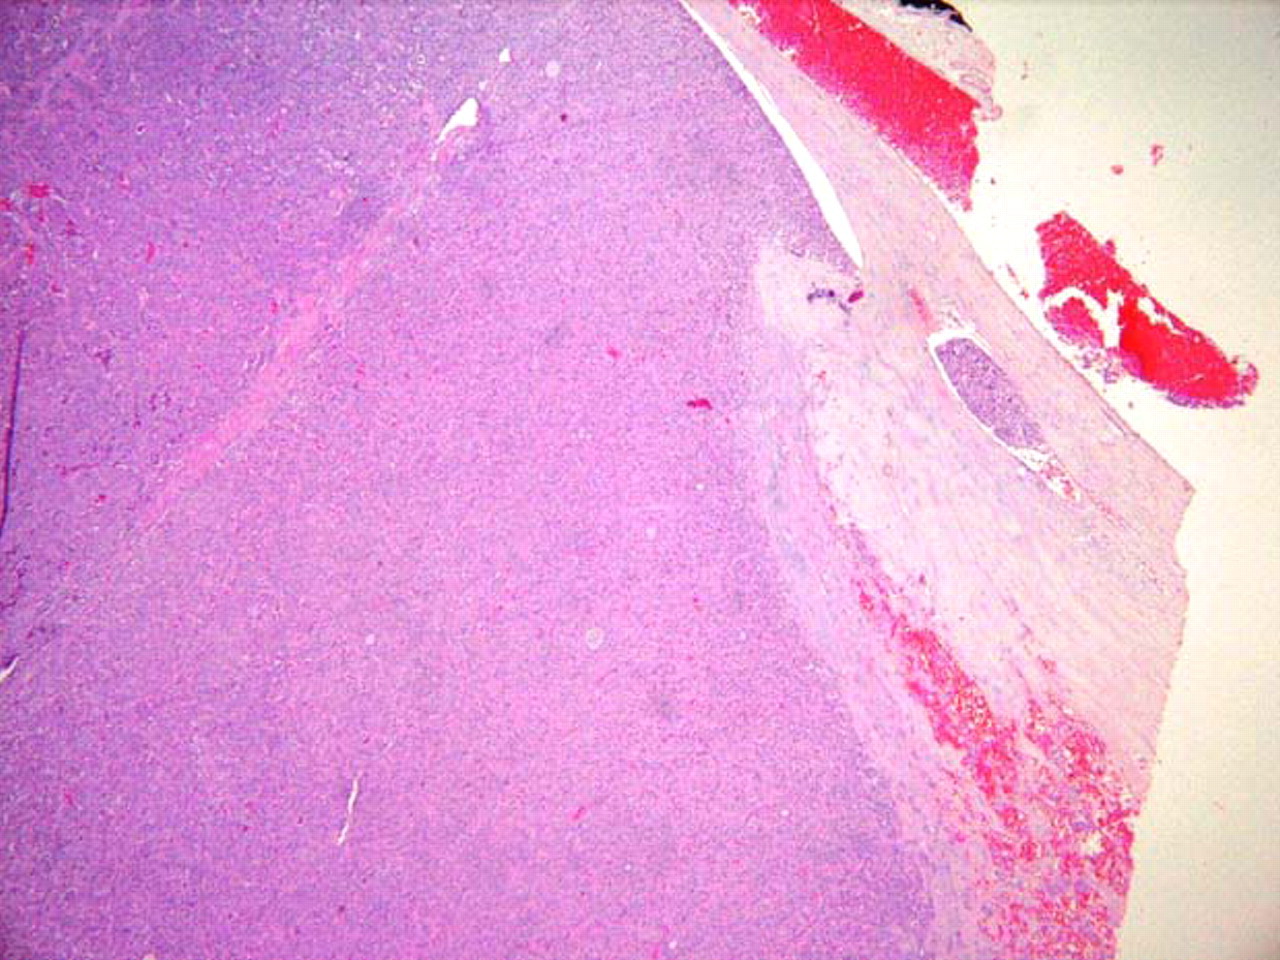

Papilar: es el tipo más común y representa el 80% de los cánceres de tiroides.[1] Generalmente, está bien diferenciado, tiende a ser multicéntrico y a afectar a los ganglios linfáticos.[Figure caption and citation for the preceding image starts]: Histopatología de un carcinoma papilar de tiroides: se puede ver un cuerpo de psamoma (flecha)CDC Image Library/Dr Edwin P. Ewing, Jr [Citation ends].